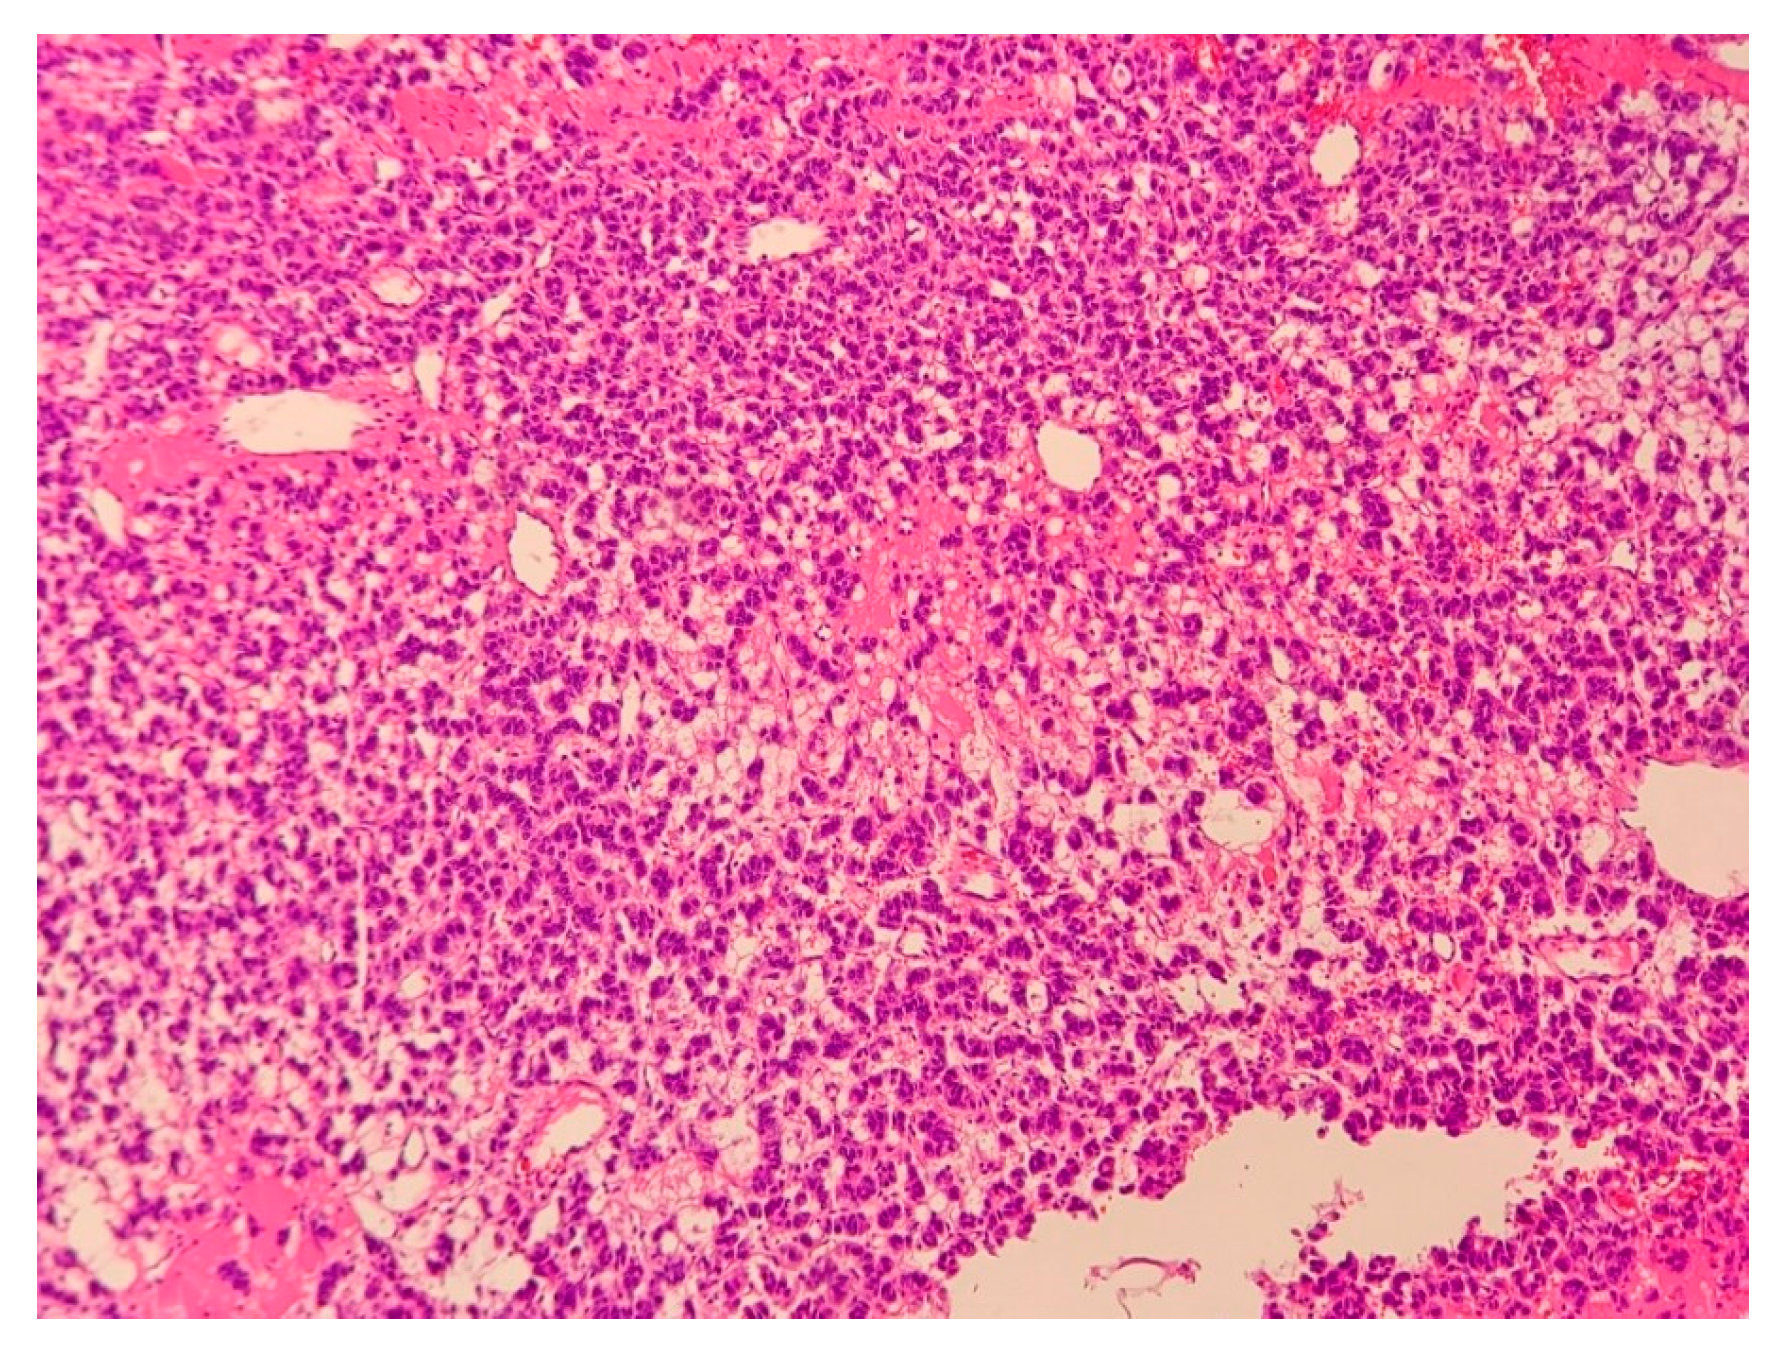

2.1. Case 1